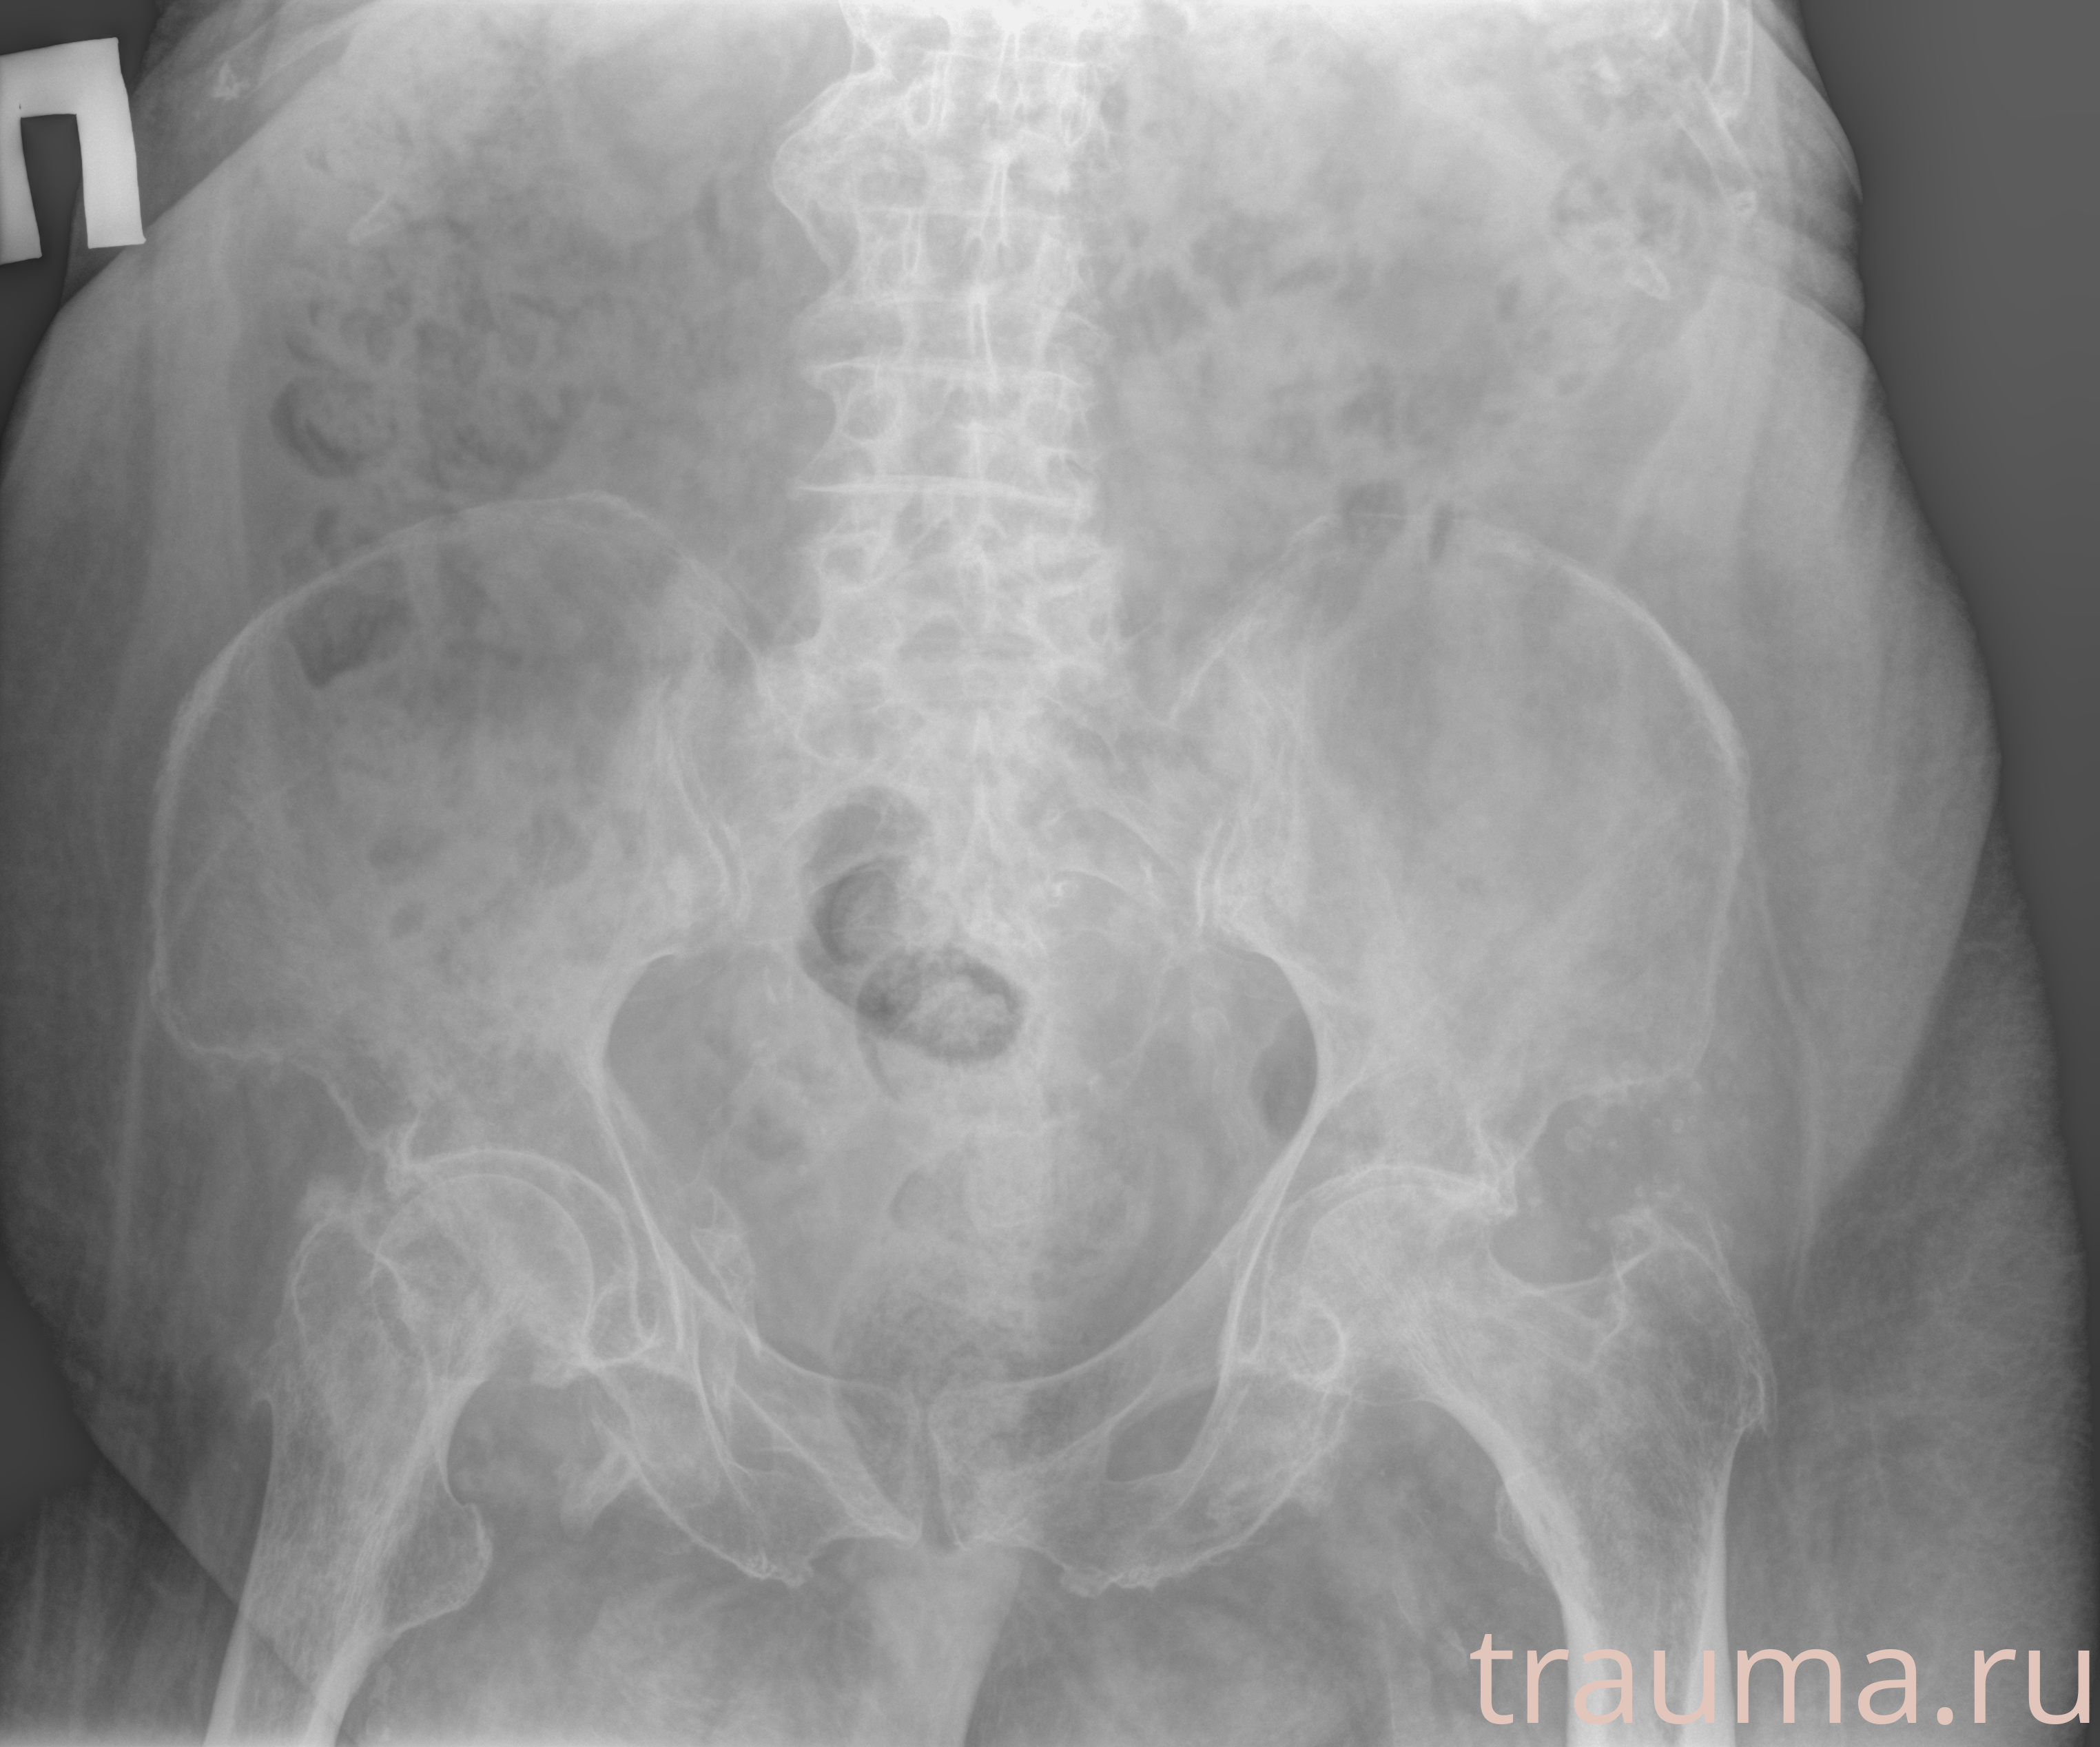

Рентгенограммы

Рентген на дому: по вашему адресу приезжает врач-рентгенолог, травматолог-ортопед с мобильным рентгеновским аппаратом, проводит диагностику травмы или заболевания, делает необходимые рентгенограммы, дает рекомендации по дальнейшему лечению. Получить качественные снимки в домашних условиях возможно благодаря уникальной методике, разработанной МосРентген Центром для института  Склифосовского

при переломе шейки бедра и пневмонии от компании МосРентген Центр - партнера Института имени Склифосовского